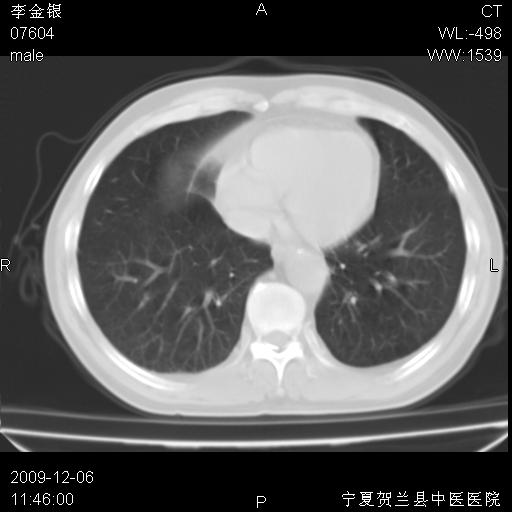

该病人 ,男,62岁,主因咳痰带血两天

考虑右肺中央型占位性病变并阻塞性肺炎.(右肺上叶支气管变窄),建议支纤镜检查.

支气管壁明显增厚 管腔狭窄,腔静脉后多个淋巴肿大,结合年龄病史考虑右肺上叶中央型肺癌并阻塞性肺炎

右肺上叶后段支气管阻塞,右上肺门占位,相应肺段阻塞性肺炎,右肺门有淋巴结肿大。诊断右肺上叶中心型肺癌,阻塞性肺肺炎、右肺门淋巴结转移。

右上叶支气管狭窄,管壁增厚,远端斑片状软组织影,病灶邻近叶间裂,叶间裂无移位。

诊断右肺中央型肺癌。

那个片影应该大部分都是病灶,病灶沿肺段支气管分支生长,后段完全显示不清、闭塞。若为不张应该伴有叶裂的移位,若为炎症应有空气支气管征。